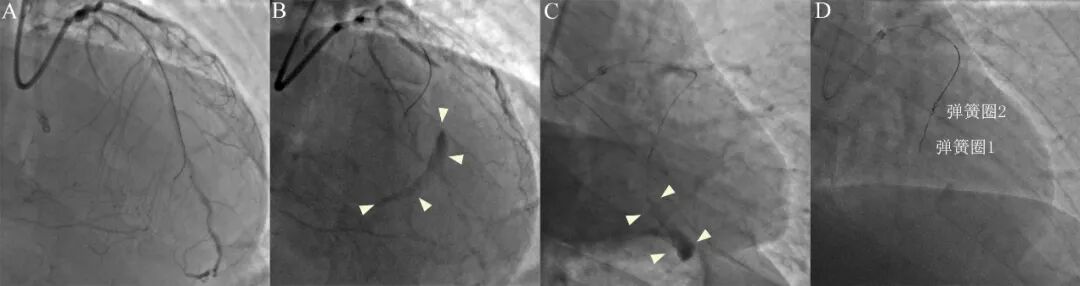

图6 弹簧圈封堵治疗心肌壁内血肿。

右冠CTO(A)尝试逆向开通,导丝在室间隔侧枝部位穿孔,形成新月形血肿(B,右肩位)。微导管超选择性造影确认穿孔血管(C),置入2*20mm弹簧圈2个封堵穿孔(D)。